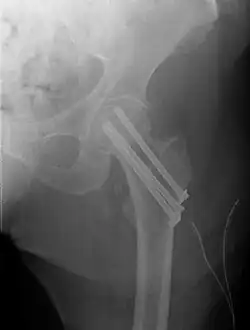

Fracture treated with cannulated screws

For low-grade fractures (Garden types 1 and 2), standard treatment is fixation of the fracture in situ with screws or a sliding screw/plate device. This treatment can also be offered for displaced fractures after the fracture has been reduced.

Fractures managed by closed reduction can possibly be treated by percutaneously inserted screws.[38]

The latest evidence suggests that there may be little or no difference between screws and fixed angle plates as internal fixation implants for intracapsular hip fractures in older adults.[42] The findings are based on low quality evidence that can't firmly conclude major difference in hip function, quality of life, and additional surgery.